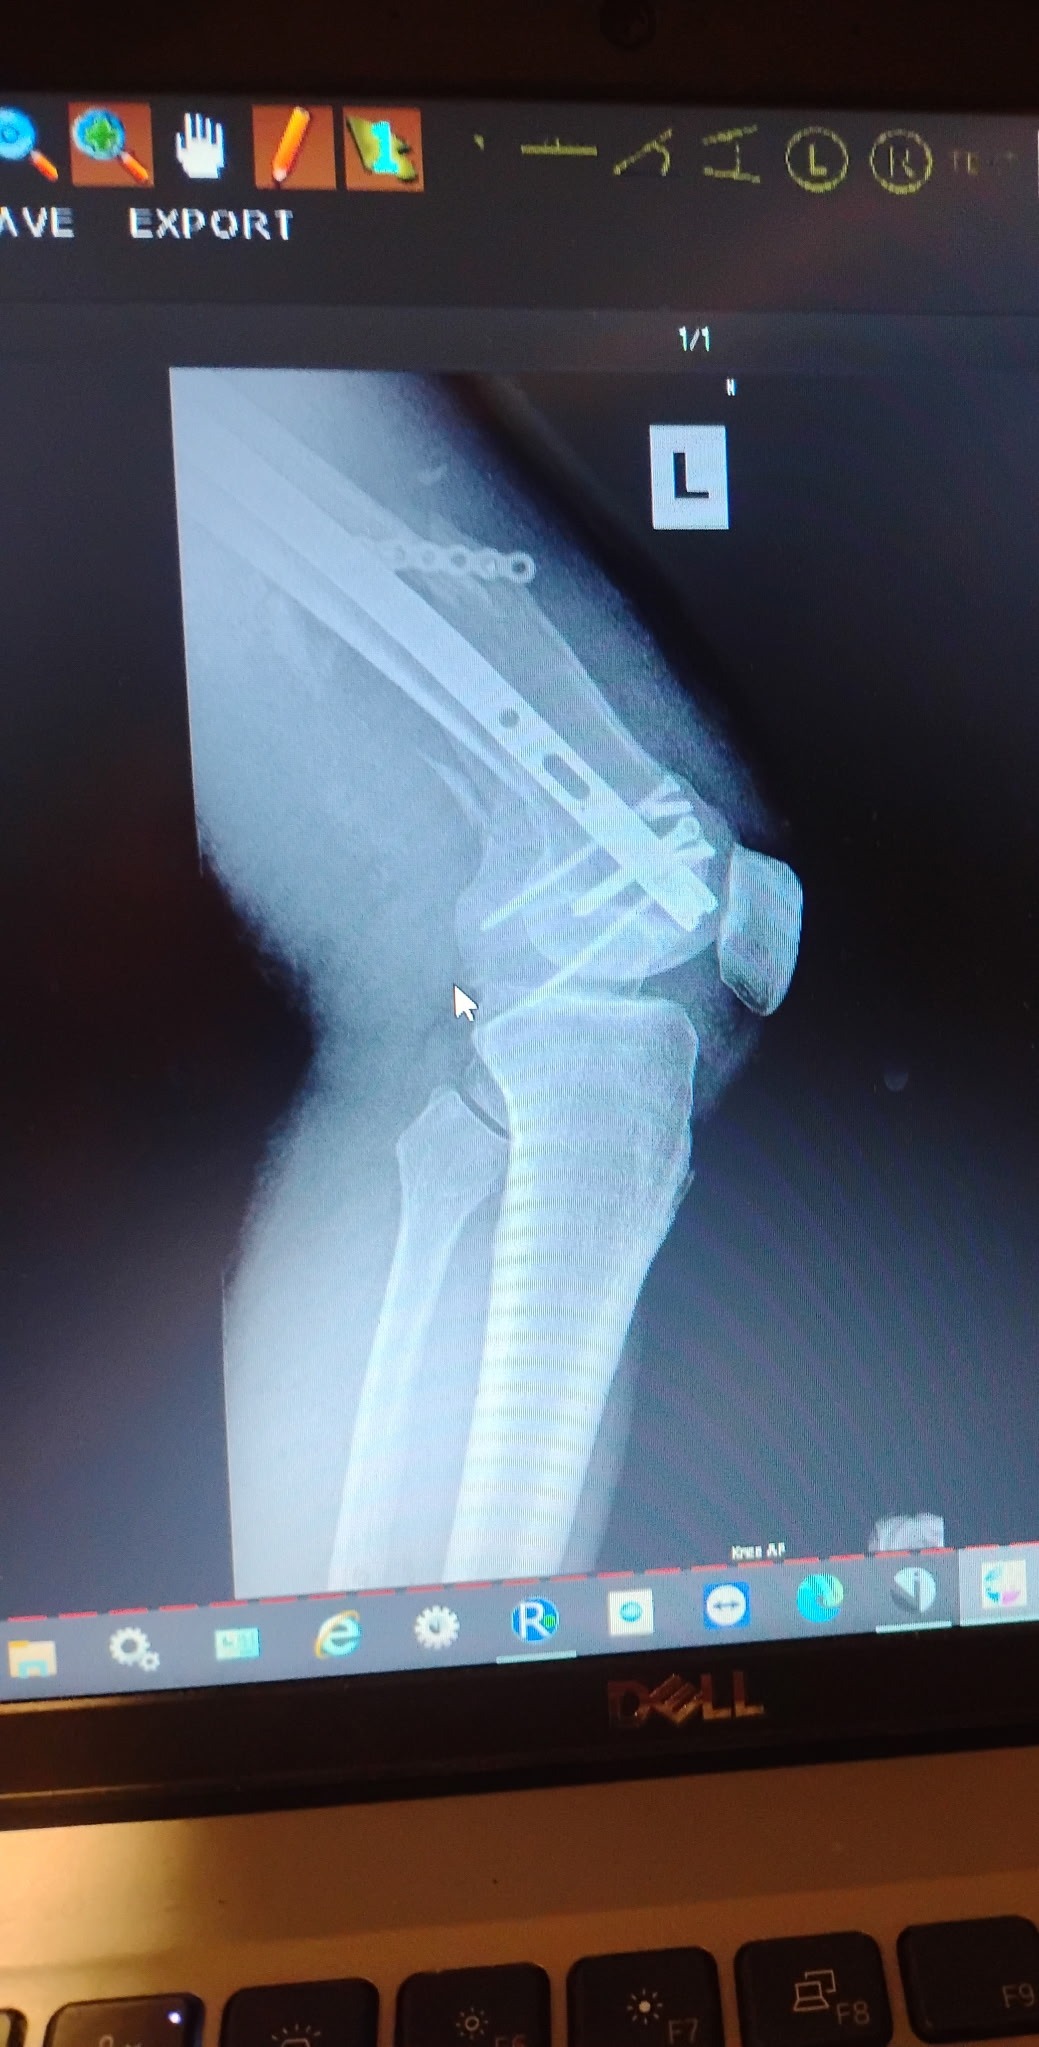

John suffered numerous life-threatening injuries, including a broken left leg and knee, a broken wrist, a fractured clavicle, broken ribs, and a broken sternum. He also experienced bleeding in his brain and had to undergo lung drainage. Due to the severity of his condition, John was placed on life support for two and a half weeks while doctors worked tirelessly to stabilize him.

As if that were not enough, complications followed. The metal rod placed in his leg to repair the fracture caused a severe infection, and his leg became septic. This has added even more medical procedures, pain, and uncertainty to an already long road to recovery.